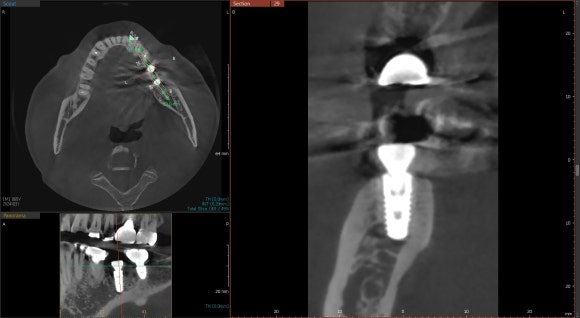

20241031

임플란트의 방향과 위치도 안정적입니다.